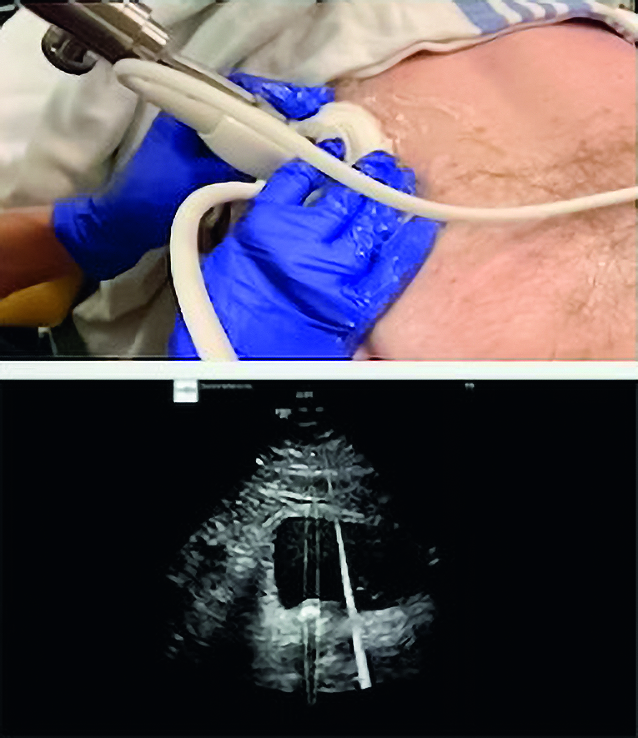

Burst-Wave oder auch Break-Wave sind modifizierte Ultraschallwellen, die mit einer hohen Frequenz von 390 kHz für eine kurze Dauer von 59 Mikrosekunden angewendet werden. In früheren Experimenten zeigte die BWL eine deutlich feinere Fragmentierung in kürzerer Zeit. Tierstudien an Schweinen zeigten nur minimale Läsionen in der Niere. Erste klinische Studien sind vielversprechend, weisen jedoch auch auf einige Einschränkungen hin. So können Steine in der oberen Kelchgruppe (sehr kleine, tief liegende oder durch Rippen oder Darm verdeckte Steine), die sonographisch nicht darstellbar sind, nicht mit BWL behandelt werden. Für die Behandlung werden nur minimal oder keine Anästhesie benötigt. Dies eröffnet die Möglichkeit, Nierensteine im ambulanten Setting zu behandeln. Eine prospektive, multizentrische klinische Studie wurde auf dem EAU 2024 vorgestellt, die das Break Wave Gerät von SonoMotion (San Mateo, CA) nutzt (▶ Abb. 1, 2).

In dieser Studie wurden 44 Patienten mit Ureter- oder Nierensteinen in fünf nordamerikanischen Zentren (USA/Kanada) zwischen August 2019 und Februar 2022 behandelt. Die Patienten wurden im Operationssaal, in der Praxis/Klinik oder in der Notaufnahme rekrutiert und behandelt. 30 Minuten Break Wave Therapie wurden unter kontinuierlicher Ultraschallortung durchgeführt. Verschiedene Therapiestufen mit bis zu 8 MPa wurden verabreicht, um die Sicherheit, Wirksamkeit und Anästhesieanforderungen zu bewerten und optimale Dosis-Einstellungen zu bestimmen. Studienziel stellt die Steinfreiheit bzw. Restfragmente ≤ 4 mm im CT dar. Es traten keine schwerwiegenden Komplikationen, Hämatome, oder Infektionen auf. Insgesamt erhielten 86 % der Patienten entweder keine Medikamente (50 %) während des Eingriffs oder nur leichte Analgesie (36 %) (z. B. Ketorolac 15–30 mg). Kein Patient musste auf Grund von Schmerzen die Behandlung frühzeitig beenden. In 88 % der Fälle trat eine Steinfragmentierung auf, wobei 70 % der Probanden entweder vollständig steinfrei oder Reststeine von ≤ 4 mm im CT aufzeigten. Die Nachbehandlungsrate lag bei 7 % innerhalb von 90 Tagen, entweder durch Stoßwellenlithotripsie (SWL) oder Ureterorenoskopie (URS). Die Patienten wurden zudem bezüglich Schmerzen und Makrohämaturie untersucht. Erste Ergebnisse zeigen hier keine Auffälligkeiten.